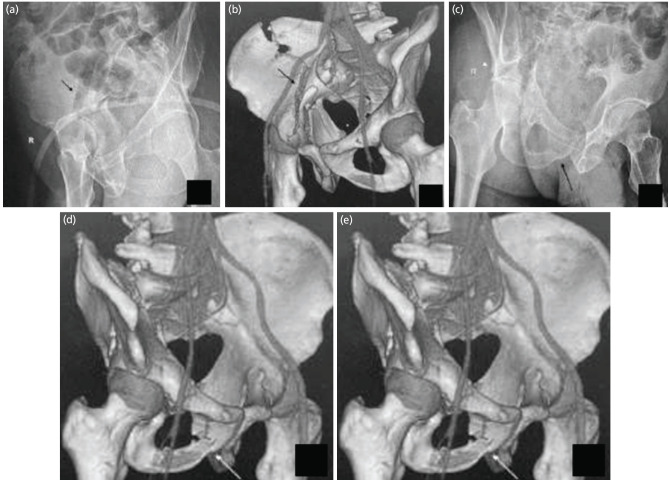

Introduction: We have devised an algorithm to assist classifying acetabulum fractures using plain radiographs. This study aimed to test if the accuracy and reliability of fracture classification increases using our algorithm in resident doctors.

Materials and methods: Seventy-two residents of eight tertiary care institutes took part in our survey. These residents were divided into three groups, Groups A, B, and C, with 31, 20, and 21 residents, respectively. Two different Collections (1 and 2) containing radiographs of twenty patients each, with known classification from CT and intra-operative findings, were prepared. Collection 1 radiographs were given to Group A and B, and Collection 2 radiographs were given to Group C. Group A residents were asked to classify the fractures using our algorithm, and Group B and C residents were asked to classify the fractures according to their understanding. Intra-observer and interobserver reliability were estimated.